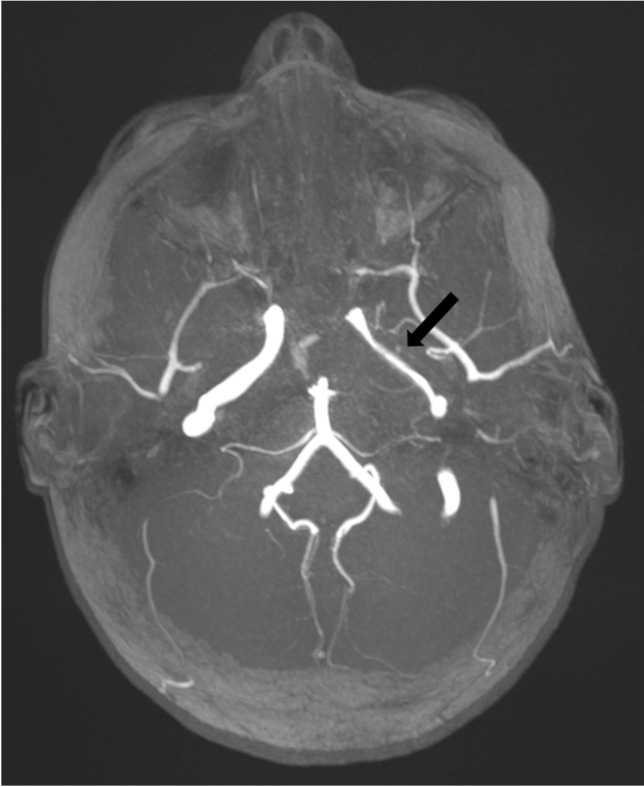

Axial multi-slab of a time-of-flight angiography 3-dimensional sequence magnetic resonance image without contrast agent administration in a 5-year-old girl with extensive abscess at the left skull base with reactive vasculitis of the internal carotid artery in the petrous part M1 (arrow) as a complication of otitis media and mastoiditis

Each of the complications assessed showed a significant increase during the winter season of 2022/2023. Severe complications especially increased during the first post-pandemic winter season. For example, vascular complications (sinus vein thrombosis and reactive vasculitis) increased from only five cases within the prior five years to 11 cases during the 2022/2023 winter season. Reactive meningitis as a complication of upper respiratory tract infection increased from four cases in the prior five winter seasons to eight cases during the post-pandemic winter season. Table 1 provides an overview of the number of cases of each imaging-based complication recorded per winter season. Figures 1, 2, 3, 4, 5, 6, 7, and 8 show examples of each of the assessed complications from the 2022/2023 winter season.